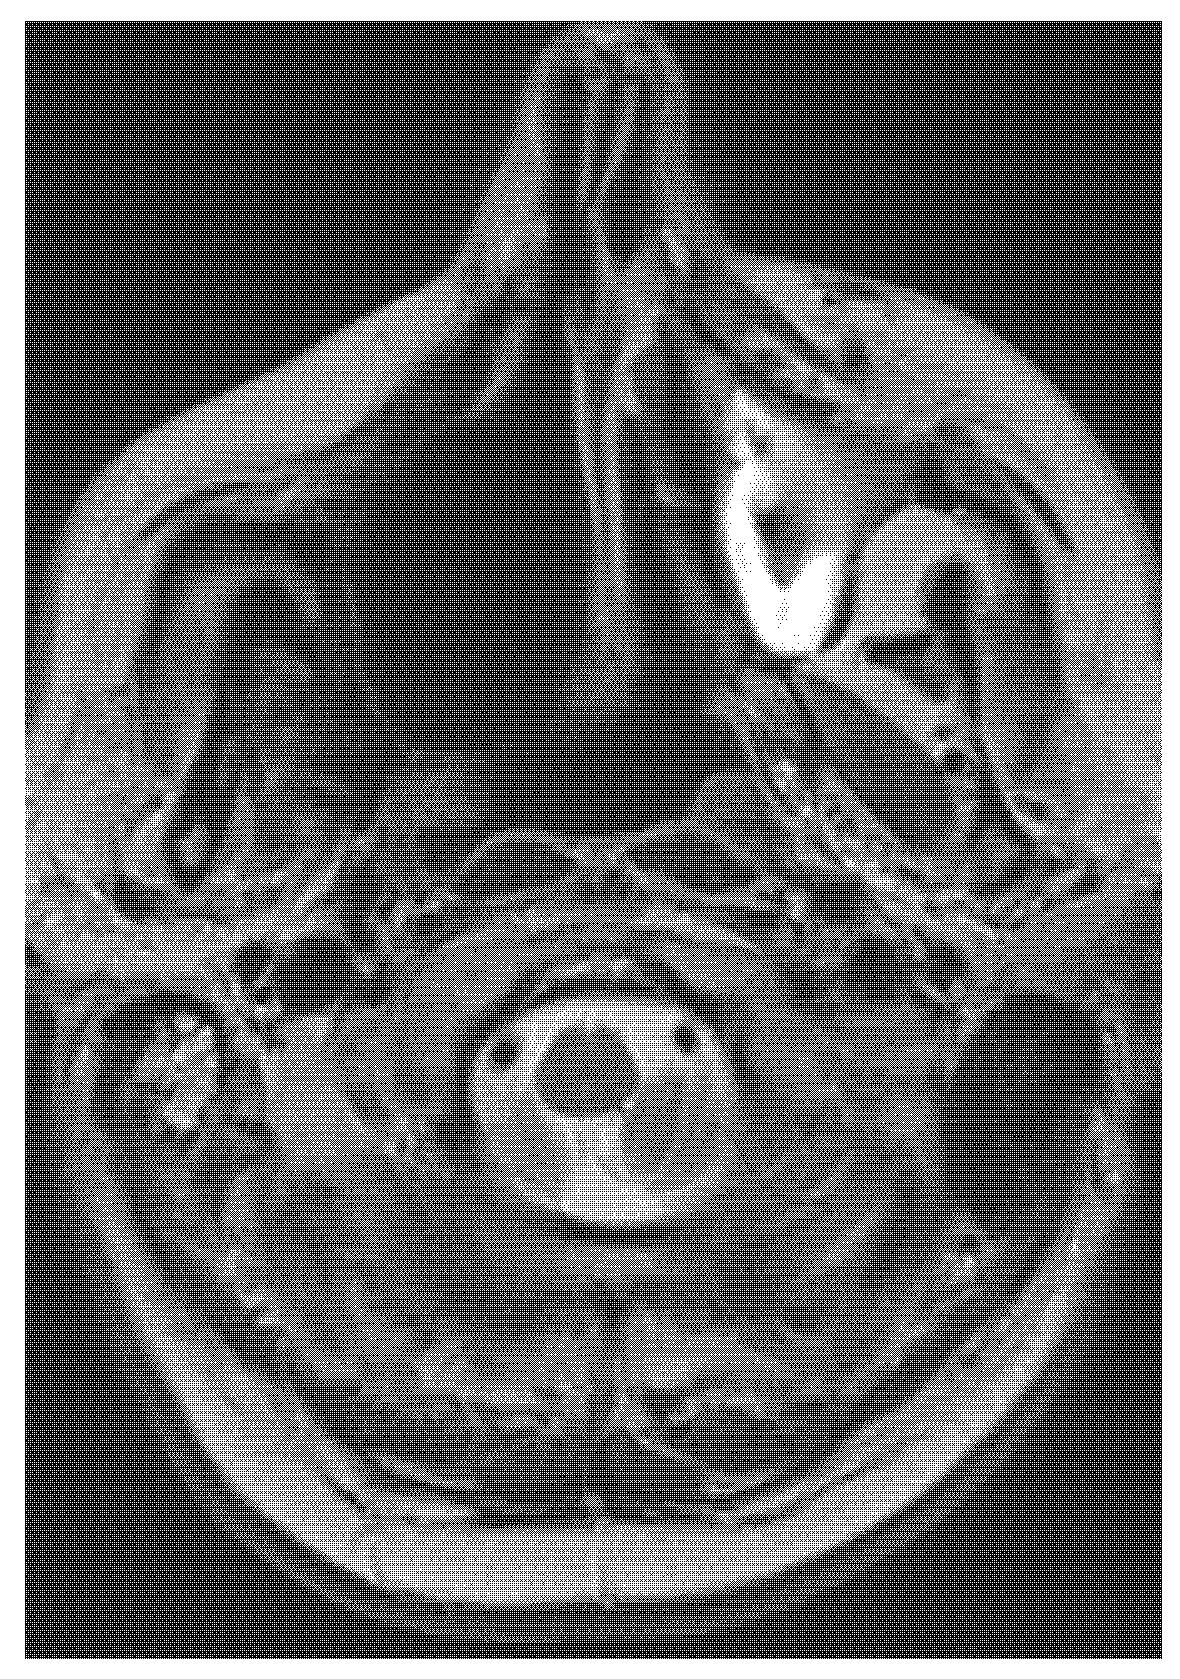

2. Case Report (Observation)

- CT, MRI scan (size, spread, and metastases of tumour mass), if necessary, PET scan, and USG.